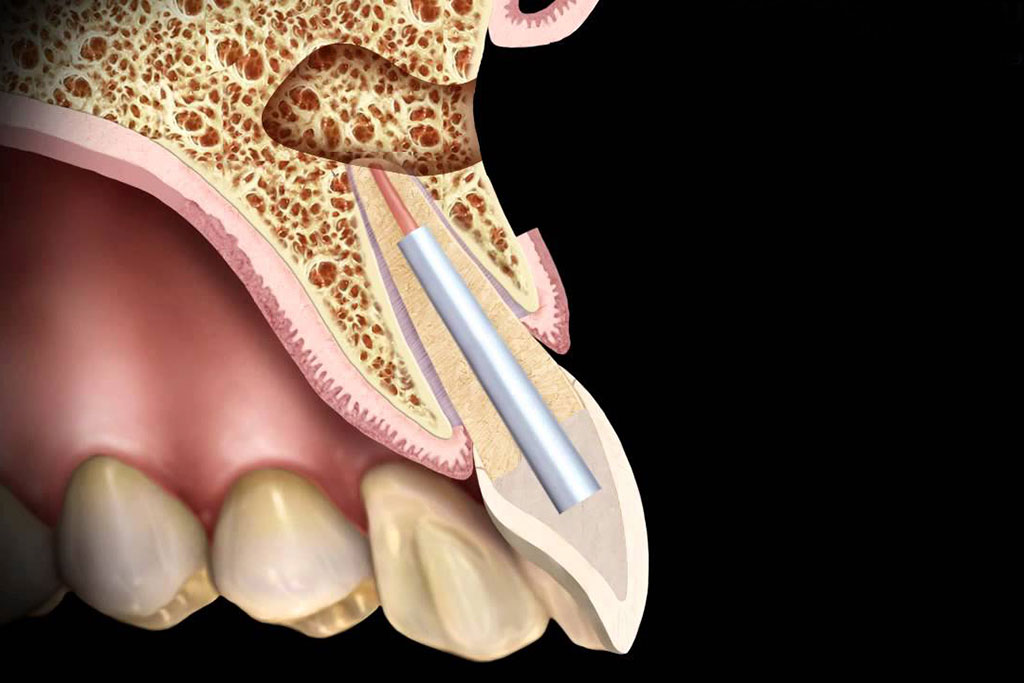

Rendelőnkben a legújabb fejlesztésű érzéstelenítési technológiát alkalmazzuk a fájdalom szabályozására. A QuickSleeper 5 egy korszerű elektronikus toll, amelyet fájdalommentes injekció beadására terveztek, ezáltal drasztikusan javítva a betegek élményét.

A hagyományos érzéstelenítő injekcióval szemben, az Quicksleeper 5 intraossealis érzéstelenítés, amely azonnal hat, a legtöbb esetben fájdalommentes, nincs az órákon át tartó kellemetlen ajak, arc zsibbadás.

A QuickSleeper az egyetlen olyan rendszer a világon, amely lehetővé teszi az érzéstelenítő könnyű befecskendezését a fogcsúcsok közelében. Exkluzív tűforgató funkcióval rendelkezik, amely lehetővé teszi, hogy könnyen és fájdalommentesen áthaladjon a kortikális csonton. Alkalmazható fogtömésnél, gyökérkezelésnél, bizonyos esetekben implantációs beavatkozásoknál is.